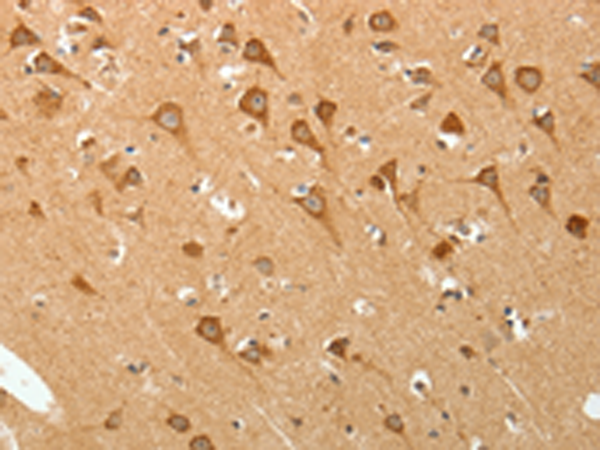

分类: 科研抗体货号: P11158别名: Fz-3应用: IHC反应种属: Human, Mouse